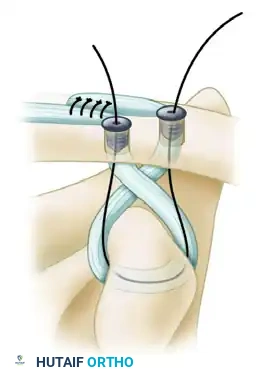

- Routing the Limbs:

- Pass the lateral limb of the graft (along with its sutures) superiorly through the first (posterior/conoid) tunnel. Cross it posteriorly so that it will ultimately form a figure-of-eight configuration.

- Feed the medial limb of the graft through the anterior (trapezoid) tunnel. Do not cross this suture; pass it directly so that it forms a circular configuration.

Graft crossing technique: The lateral limb is crossed posteriorly to create a figure-of-eight, mimicking the complex multi-planar vectors of the native CC ligaments.